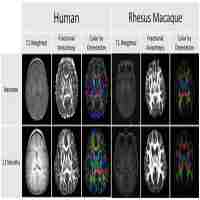

| Abstract | Brain atlases are widely used in experimental neuroscience as tools for locating and targeting specific brain structures. Delineated structures in a given atlas, however, are often difficult to interpret and to interface with database systems that supply additional information using hierarchically organized vocabularies (ontologies). Here we discuss the concept of volume-to-ontology mapping in the context of macroscopical brain structures. We present Java tools with which we have implemented this concept for retrieval of mapping and connectivity data on the macaque brain from the CoCoMac database in connection with an electronic version of “The Rhesus Monkey Brain in Stereotaxic Coordinates” authored by George Paxinos and colleagues. The software, including our manually drawn monkey brain template, can be downloaded freely under the GNU General Public License. It adds value to the printed atlas and has a wider (neuro-)informatics application since it can read appropriately annotated data from delineated sections of other species and organs, and turn them into 3D registered stacks. The tools provide additional features, including visualization and analysis of connectivity data, volume and centre-of-mass estimates, and graphical manipulation of entire structures, which are potentially useful for a range of research and teaching applications. |

| Subject Keyword | Rhesus macaque atlas Visualization Neuroanatomy Connectivity Neuroimaging Primate brain Database interfaces Ontology Path analysis Computational Biology/Bioinformatics Biotechnology Neurology Computer Application in Life Sciences Neurosciences |